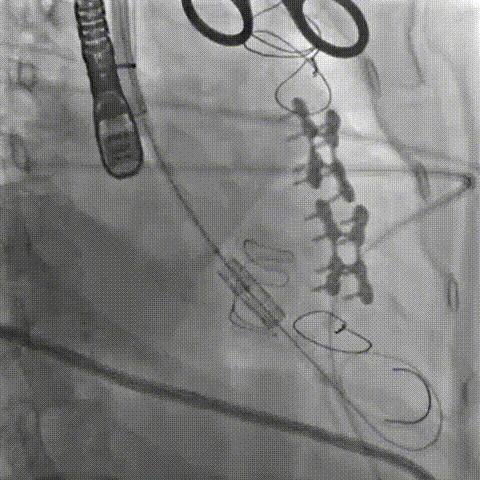

二尖瓣病例:

患者女性,73岁,既往二尖瓣位植入27# Epic猪瓣,超声提示二尖瓣人工瓣膜衰败伴重度关闭不全,瓣叶连枷。该患者还合并重度贫血、低白细胞、低血小板、多囊肝、多囊肾、永久起搏器植入术后、心功能NYHA III级、营养状况极差,术前STS评分12.1%,属于常规外科手术极高风险患者。术前经详尽影像学评估及病例讨论,考虑到患者既往经房间隔切开植入二尖瓣人工瓣膜,房间隔疤痕钙化严重增加穿刺手术风险,决定采用更安全的经心尖途径植入27号Renato球扩式瓣中瓣。

手术耗时约1小时,全程生命体征平稳,几乎无出血。瓣中瓣植入位置理想,功能表现出色:左房压自术前50/15/27mmHg降至21/11/15mmHg,二尖瓣平均流速自2.2m/s降至1.4m/s,二尖瓣平均跨瓣压差自6mmHg降至3mmHg。

▲球扩二尖瓣 ▲左室造影